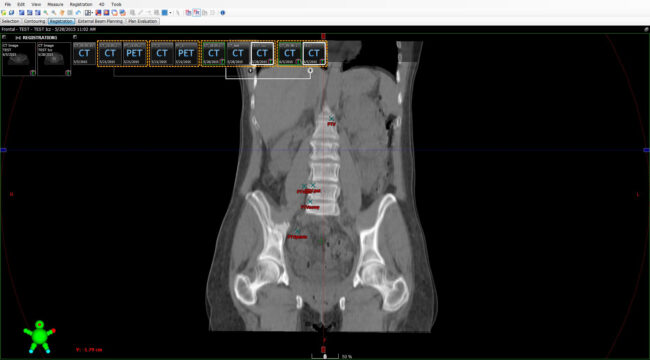

Streszczenie Radioterapia w leczeniu raka szyjki macicy odgrywa bardzo dużą rolę. Jej zastosowanie oraz objęcie obszarem tarczowym napromienianych struktur zależy od zaawansowania choroby nowotworowej. Zastosowanie nowoczesnych technik planowania oraz weryfikacji ułożenia pacjenta pozwala na ograniczenie marginesu tkanek zdrowych i toksyczności całego leczenia radioterapeutycznego. Trzeba jednak brać pod uwagę wystąpienie czynników wpływających na dokładności przeprowadzonego leczenia. Takim…